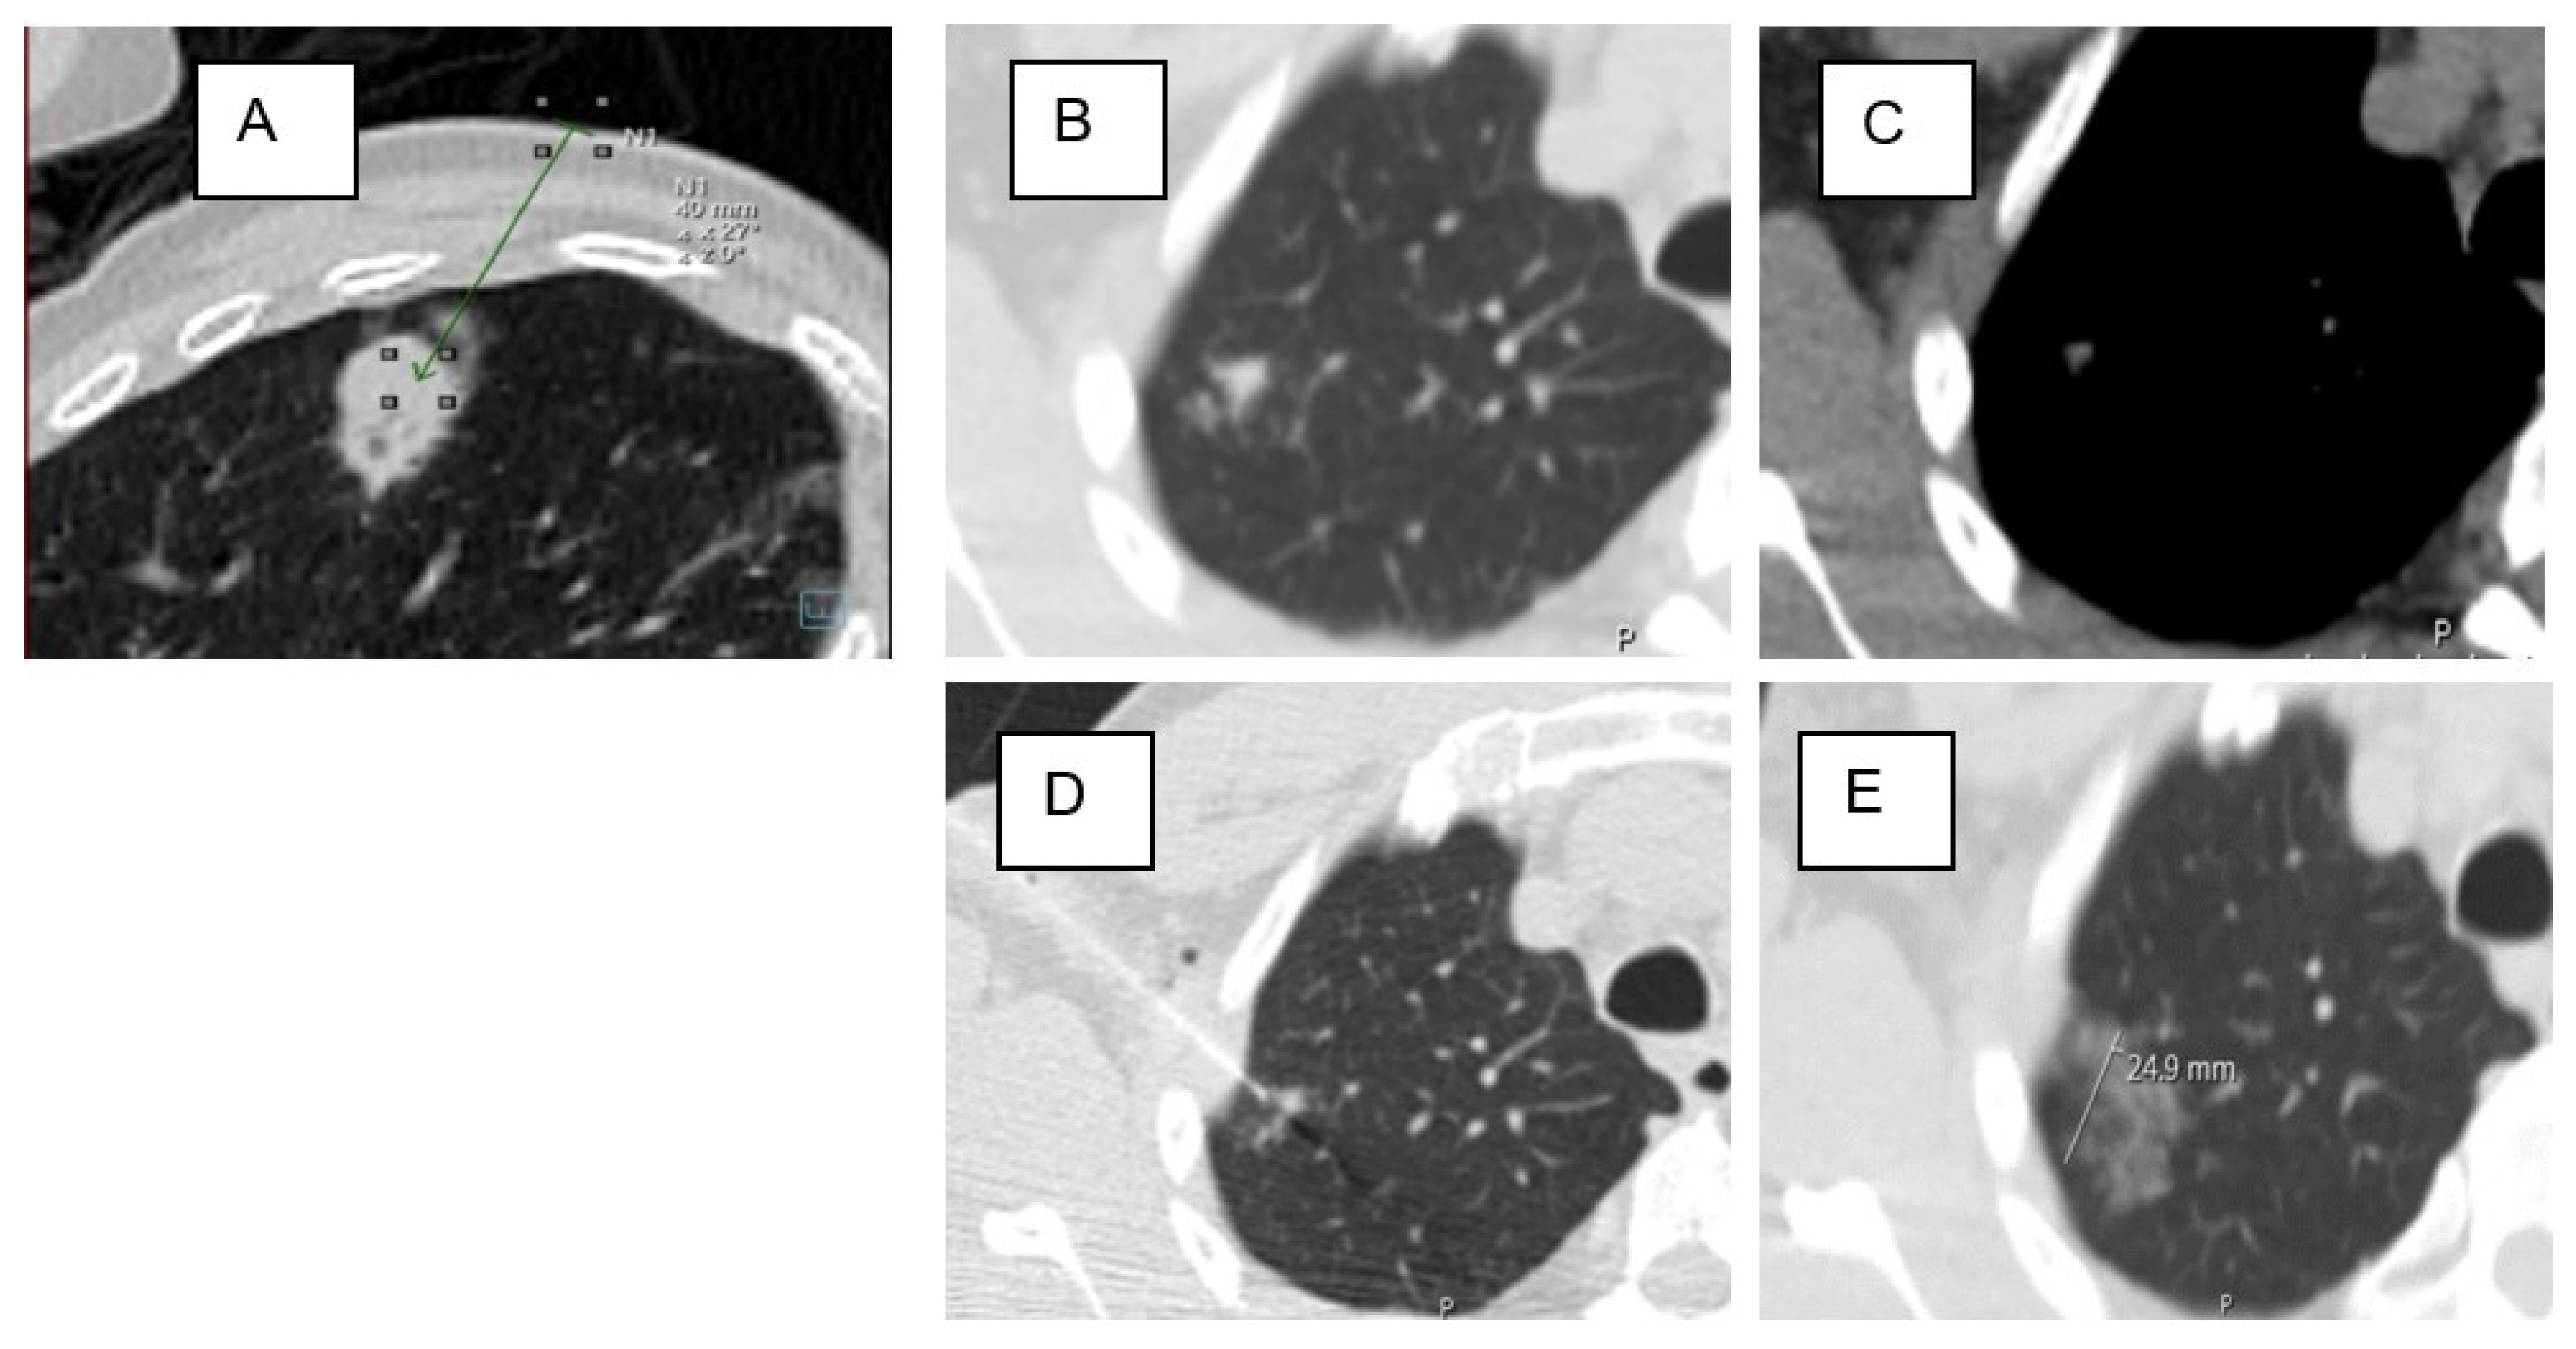

| Distance SL (mm) | 63.11 | ±21.32 | 61 | 21.15 | 69.1 | ±21.01 | 0.074 |

| Distance PL (mm) | 16.57 | ±14.33 | 15.26 | ±14.84 | 20.3 | ±12.24 | 0.035 * |